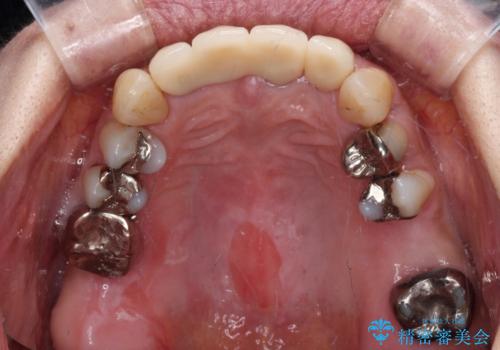

また、前歯に抜歯が必要な歯があったため、抜歯をし、傷の治りを待ってオールセラミックブリッジにて補綴治療を行うこととしました。

一番気になっていた隙間が埋まり、不快感から解放されました。